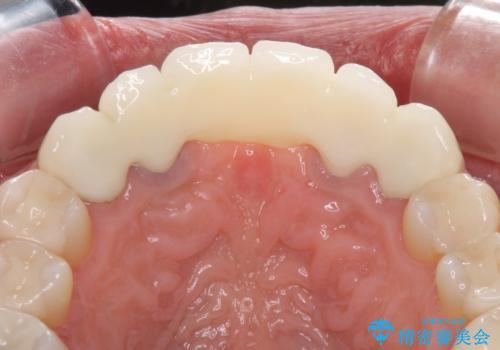

金属を使用した前歯のブリッジや奥歯の銀歯は全てオールセラミッククラウンまたはセラミックインレーとし、左下の奥歯はインプラントにより治療を行うこととしました。

初診カウンセリングを含めて13回の通院で治療を終えることができ、患者様には大変満足していただきました。